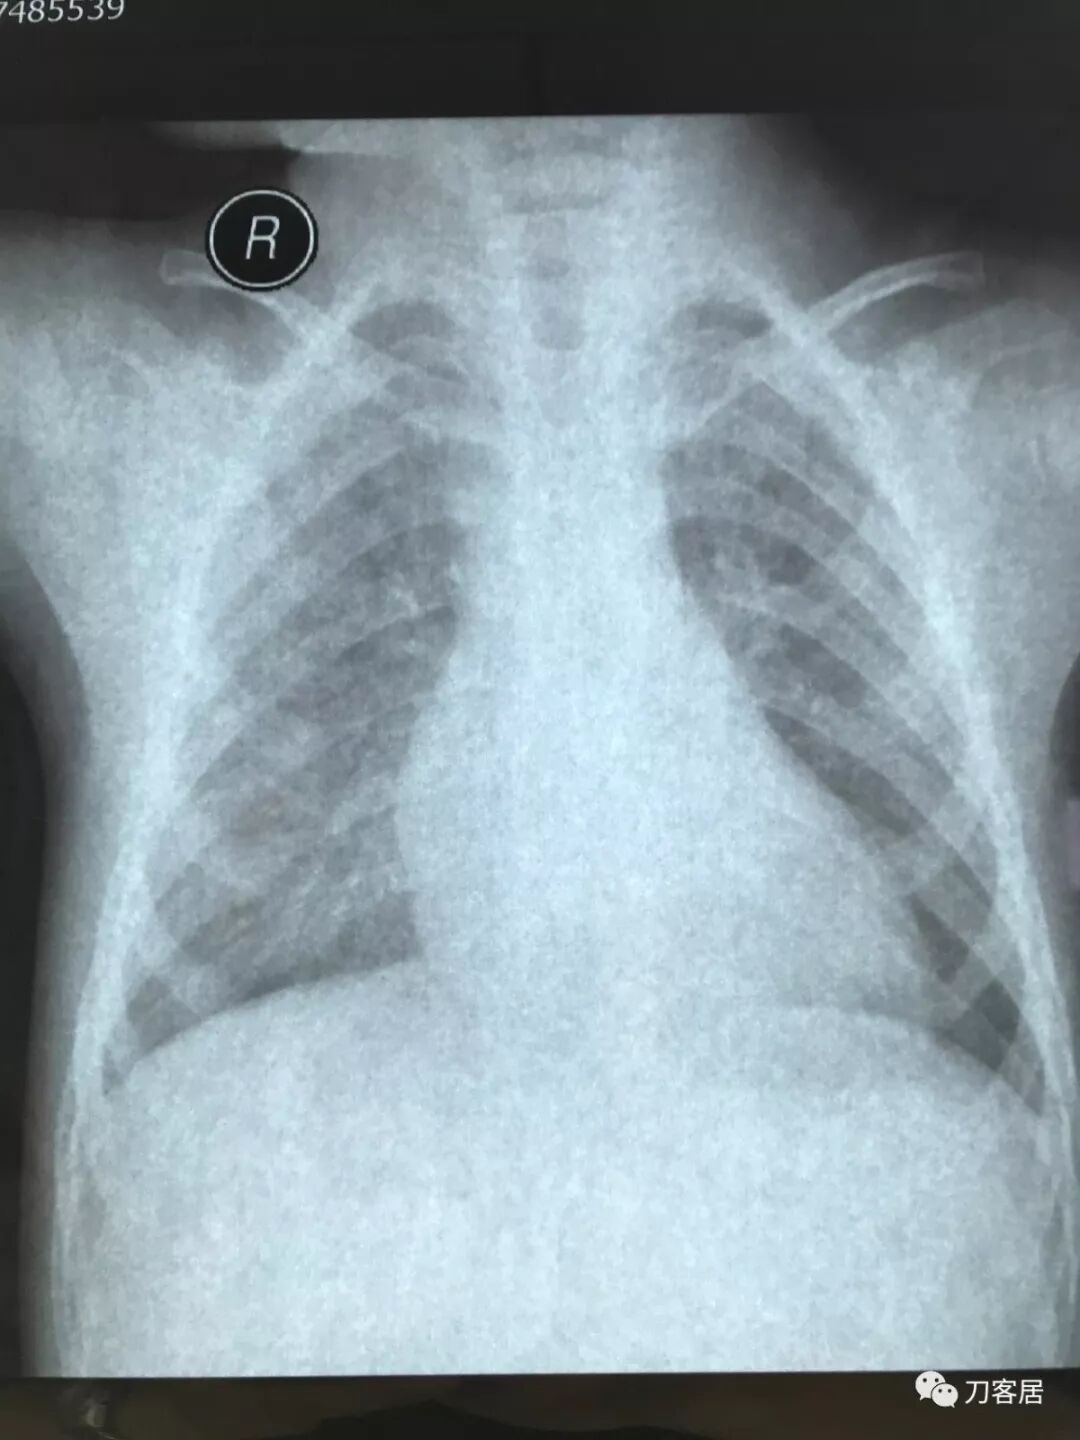

拍片子时,如果一张片子上有两张图像的时候,合起来拍一张(图15),分开再各拍一张(图16,图17)

图16

图17

拍摄时,尽可能的将片子上的文字信息拍摄清楚,并将左右拍摄清楚(片子上有标R,表示右侧right,L, 表示左侧left的意思),每张片子上的文字都能按照阅读习惯拍正确,不要拍反。